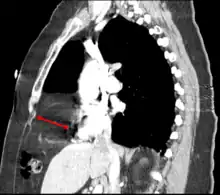

Morgagni hernia

This rare anterior defect of the diaphragm is variably referred to as a Morgagni, retrosternal, or parasternal hernia. Accounting for approximately 2% of all CDH cases, it is characterized by herniation through the foramina of Morgagni which are located immediately adjacent and posterior to the xiphoid process of the sternum.[4]